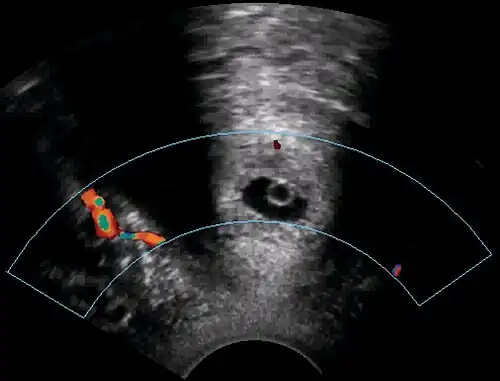

Trans-section of the cervix with Doppler ultrasonography, showing that the pregnancy (center) is at the same level as the uterine artery (giving a colored pattern to the right on doppler).

A woman in her 20s came to the gynecologic clinic because of a positive pregnancy test and a history of a previous ectopic pregnancy. The vaginal ultrasonography performed by Dr. Jesper Agrell showed a gestational sac in the cervix as displayed in the sagittal plane. The corpus of the uterus is located at right in the image. There was a discernible heartbeat, and the gestational sac diameter corresponded to a gestational age of 5 weeks. The distance from the gestational sac to the external orifice was only 15 millimeters.